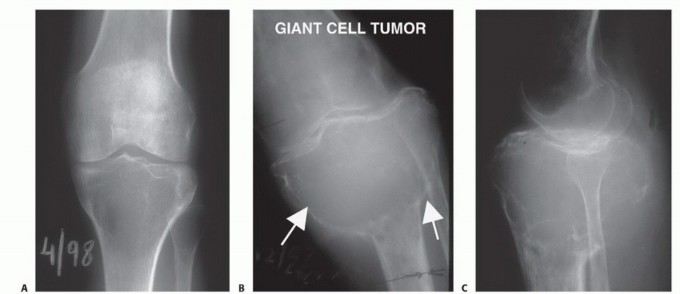

- ورم الخلايا العملاقة (Giant Cell Tumor - GCT): يُعد من الأورام الحميدة ولكنه قد يكون عدوانياً محلياً، ويمكن أن يُسبب تدميراً كبيراً للعظم وقد يتكرر بعد الاستئصال. في حالات نادرة جداً، قد يتحول إلى ورم خبيث.

- الأشعة السينية (X-rays): هي الخطوة الأولى، وتُظهر التغيرات في بنية العظم، مثل التدمير العظمي، أو تكوين العظم الجديد، أو رد فعل السمحاق.

- التصوير بالرنين المغناطيسي (MRI): يُعتبر الأداة الأكثر أهمية لتحديد مدى انتشار الورم داخل العظم، وفي الأنسجة الرخوة المحيطة، وعلاقته بالأوعية الدموية والأعصاب. يُساعد في تحديد هوامش الاستئصال الجراحي.